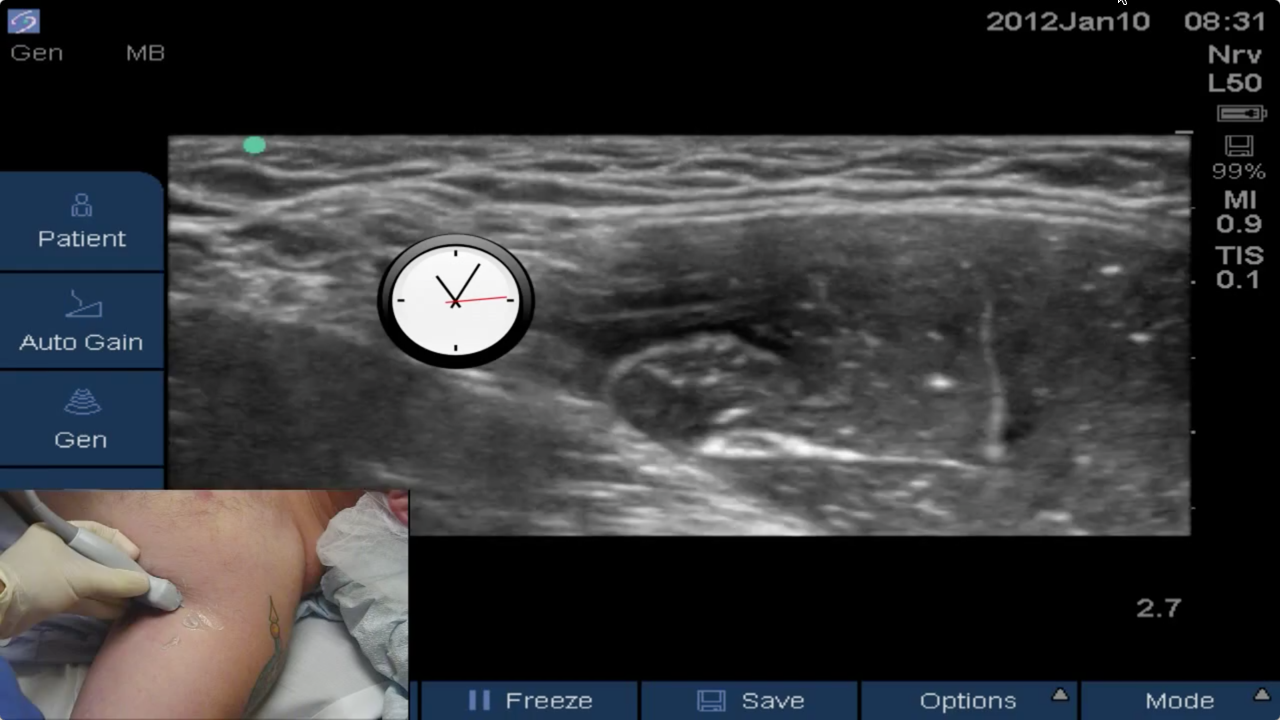

Late Branching Musculocutaneous NerveIn this video by Dr. Saad Kamal, with an introduction by Dr. Brandon Winchester, we demonstrate an important anatomic variation occasionally found during axillary brachial plexus blocks: a late branching musculocutaneous nerve off the lateral cord. When this variation occurs it results in difficu...

Axillary Virtual Ultrasound WorkshopIn this new Virtual Ultrasound Workshop video Dr. Brandon Winchester explains tips and tricks for the successful and safe placement of axillary brachial plexus blocks. The BLOCKJOCKS Virtual Ultrasound Workshop comprehensively discusses and demonstrates scanning & technique considerations for ...

Ultrasound-Guided Axillary Brachial Plexus BlockBrandon Winchester performs an ultrasound-guided axillary brachial plexus block with an axillary ring infiltration for a distal biceps tendon and carpal tunnel release.

Axillary BlockBlock of the Day #10: Brandon Winchester performs an US-guided axillary block for finger/wrist surgery at Andrews Institute.